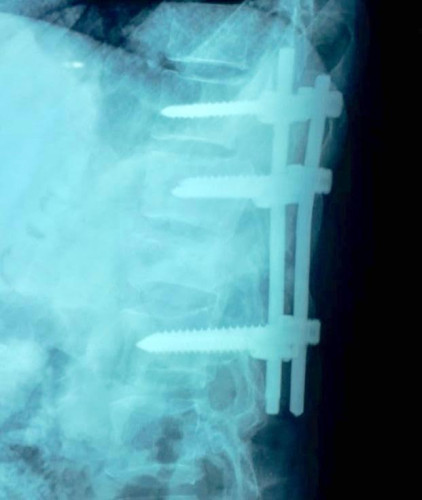

وأوضحت صحة الجوف, أن المصاب تعرض لحادث مروري حيث تم إسعافة إلى مستشفى طبرجل العام وعلى الفور قام الفريق الطبي بتشخيص الإصابة التي كادت أن تؤدي إلى أذية في النخاع الشوكي وخطر التعرض للشلل في الأطراف السفلية، حيث تم نقل المريض إلى غرفة العمليات ، لإجراء تثبيت للكسر في الفقرات خلال الوقت المناسب بواسطة شرائح معدنية ومسامير حيث أستغرق العمل الجراحي 90 دقيقة ، والمصاب حالياً بصحة جيدة ووضعه مستقر ولله الحمد وتحت المتابعة الطبية والعلاج التأهيلي.